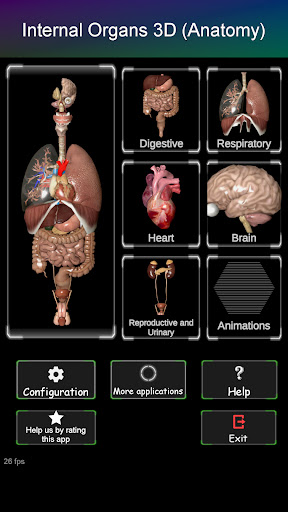

Shows a 3D anatomical model of the main organs of the human body and a description of each one.

What's in the app?

* Digestive system, including the stomach, small intestine, large intestine, and an animation of this system.

* Respiratory system, which includes the trachea, bronchi, lungs and an animation of this system.

* Reproductive system, which includes the male and female reproductive organs.

* Brain, which includes the brain, cerebellum, and brain stem.

* Heart, which includes the atria, ventricles, aorta and an animation of this organ.

* Easy to access and navigate (zoom, 3D rotation).

* Hide or show information.

* Compare male and female organs.

* Descriptions of each organ.